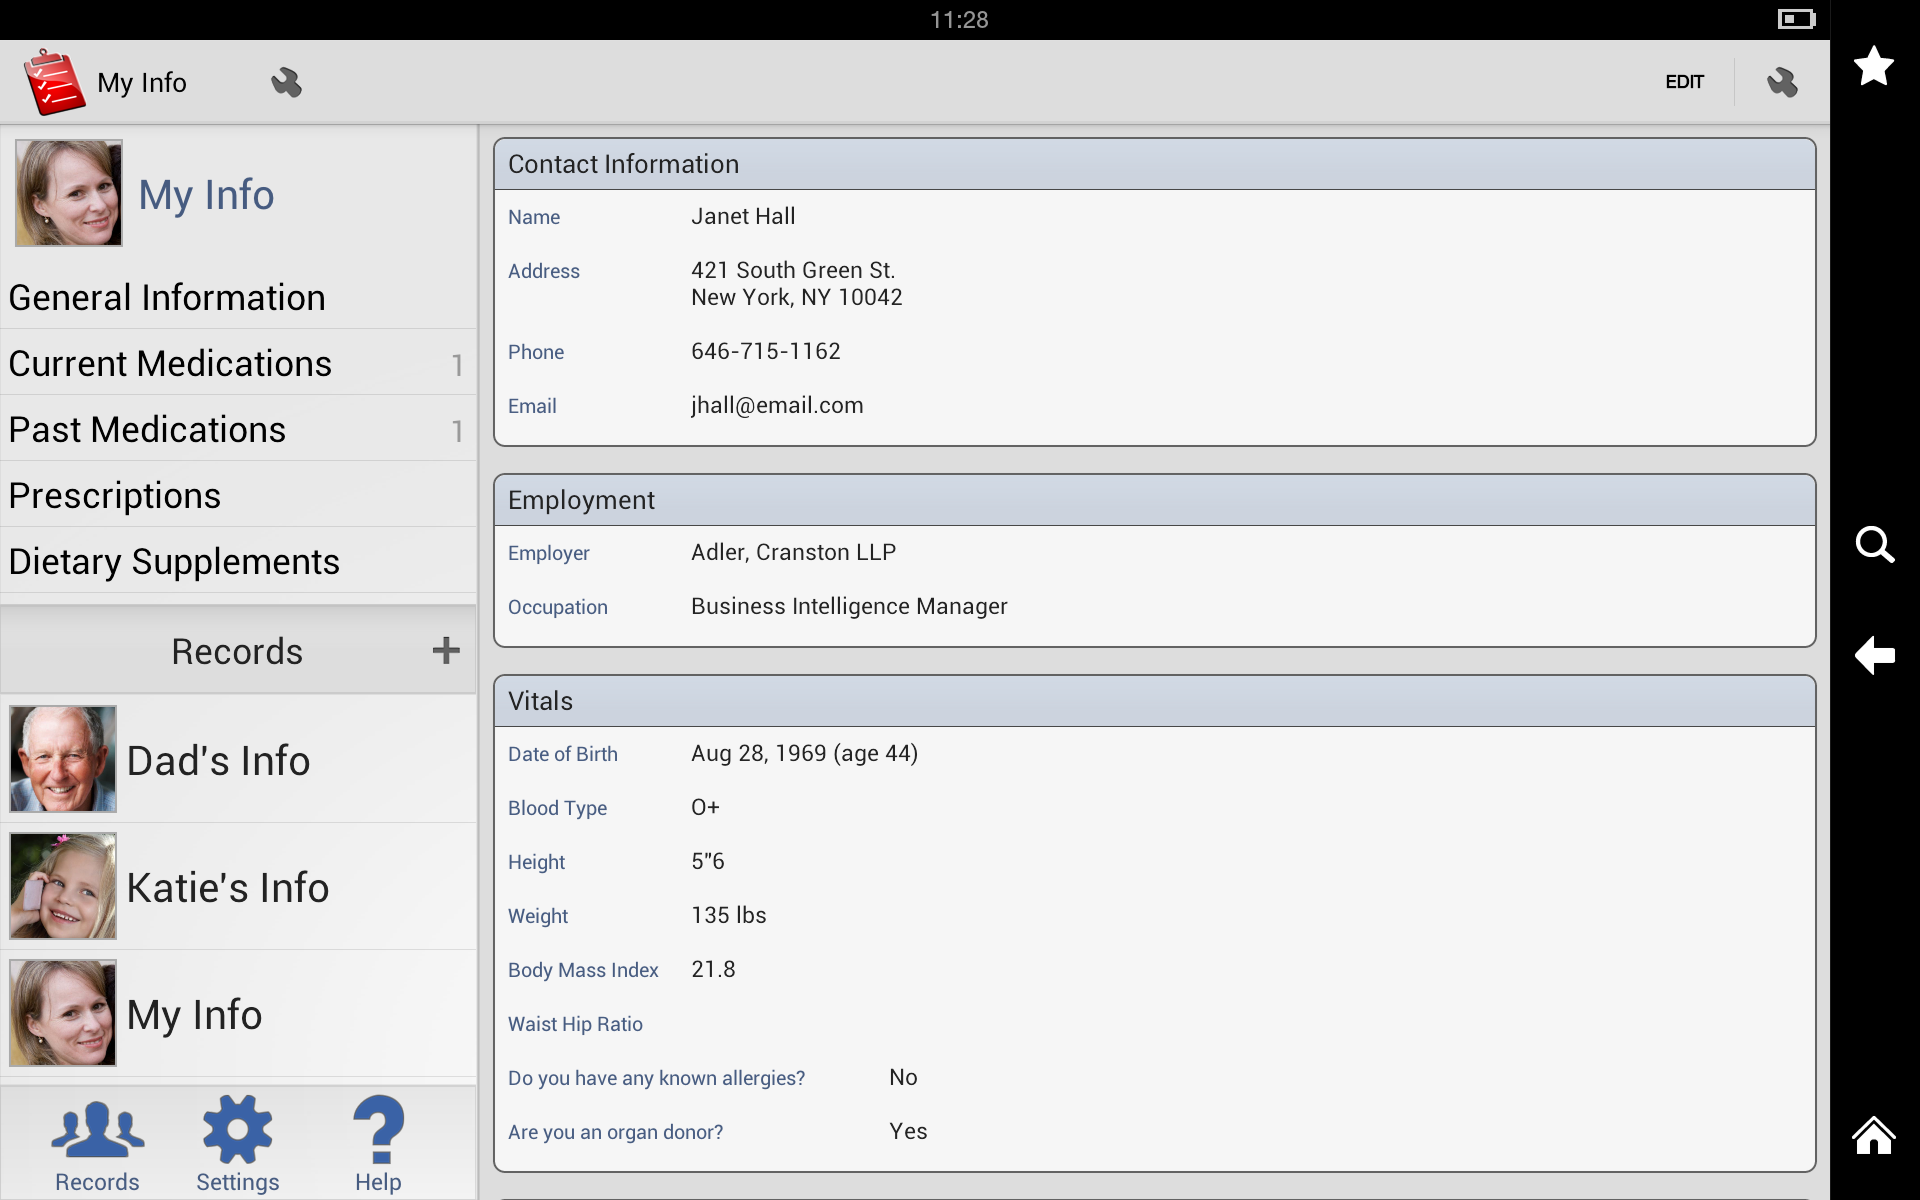

My Medical is a digital organizer that allows you to keep all of your medical information in one place. With My Medical, you can store information such as your medical history, medication list, test results, and doctor’s contact information. You can also use My Medical to track symptoms, appointments, and procedures. My Medical is available for both iOS and Android devices, making it a convenient way to manage your health information on-the-go.

Medical History

My Medical allows you to create a detailed medical history that includes information such as surgeries, illnesses, vaccinations, and family history. You can also add notes to your medical history to provide additional context.

Doctor’s Contact Information

My Medical allows you to store the contact information for all of your doctors, including their names, phone numbers, and addresses. You can also add notes about each doctor, such as their specialties or any particular instructions they’ve given you.

Emergency Contacts

With My Medical, you can store the contact information for your emergency contacts, such as family members or close friends. You can also add notes about each emergency contact, such as their relationship to you or any specific instructions.

With My Medical, you can store the contact information for your emergency contacts, such as family members or close friends. You can also add notes about each emergency contact, such as their relationship to you or any specific instructions.

User Interface

My Medical has a clean, intuitive interface that makes it easy to navigate and use. The app is organized into tabs for each section, making it easy to find the information you’re looking for. The buttons and menus are clearly labeled, and the app uses intuitive icons to represent different functions.